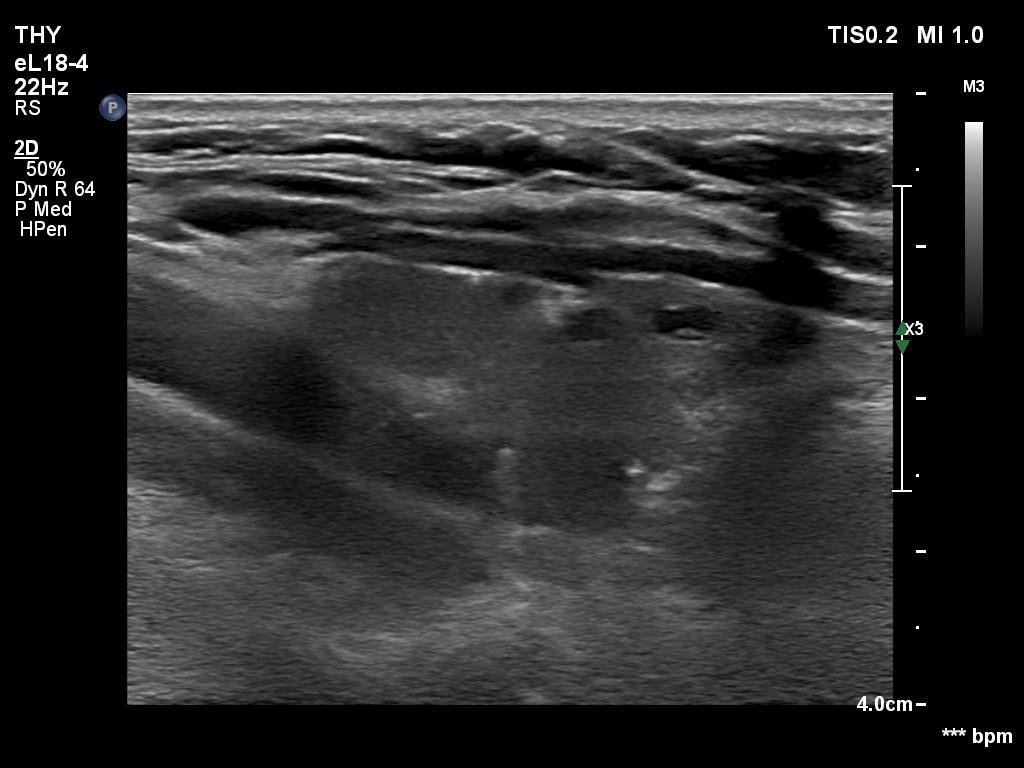

Lymphocytic thyroiditis - case 1441

Left lobe

Focal form of lymphocytic thyroiditis is presented. The thyroid has numerous discrete, hypoechoic lesions which correspond to more active foci of thyroiditis. The interpretation of the relatively large ventral hypoechoic area in the left lobe (right upper image can cause problem), however, longitudinal scan decides the issue: this field cannot be a pathological nodule.